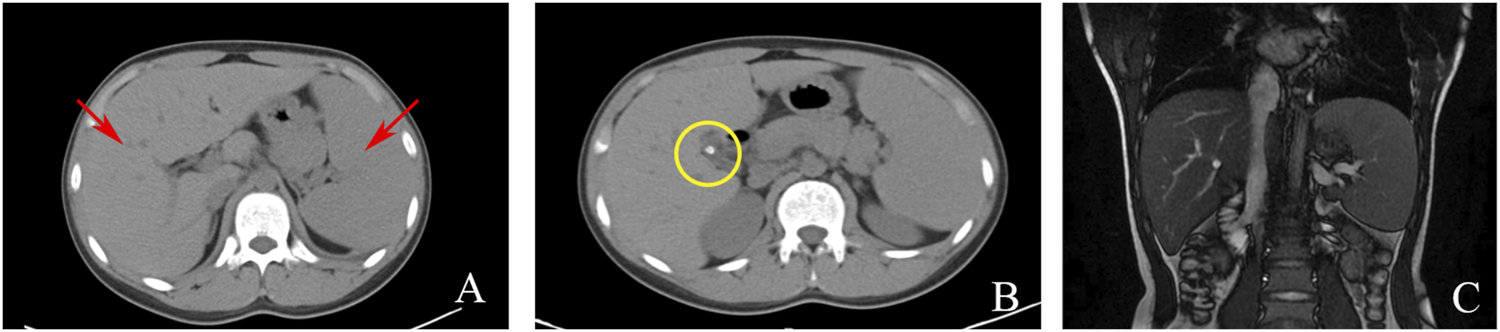

Serological and laboratory investigations were conducted to rule out various conditions including viral hepatitis, autoimmune hepatitis, primary biliary cholangitis, Wilson disease, and liver damage associated with hyperthyroidism. Tests for herpes simplex virus, cytomegalovirus, and Epstein-Barr virus antibodies yielded negative results. Anemia-related tests, including those for hemolytic anemia, glucose-6-phosphate dehydrogenase deficiency (G-6-PD), paroxysmal nocturnal hemoglobinuria (PNH), and thalassemia genetic testing, were also negative. Blood routine analysis revealed mild anemia and reticulocytosis. Examination of the blood cell smear indicated slight variability in the size of red blood cells and the presence of polychromic red blood cells. Serum ferritin levels were elevated, while serum iron levels remained within the normal range (Table 1). Magnetic resonance cholangiopancreatography (MRCP) demonstrated normal intrahepatic and extrahepatic biliary tree structures, as well as a normal pancreatic ductal system (Figure 1). Additionally, a whole abdomen computed tomography (CT) scan revealed the presence of multiple gallbladder stones, increased liver parenchymal density, and an enlarged spleen (Figure 1).

FIGURE 1

Imaging examinations: (A) CT scan showing liver and spleen enlargement (red arrow); (B) CT scan showing gallbladder neck stones (yellow circle); (C). MRCP showing a normal intrahepatic and extrahepatic biliary tree and pancreatic ductal system.